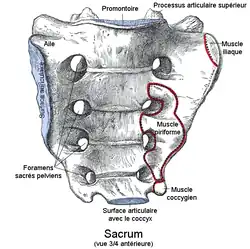

Le sacrum, chez les vertébrés terrestres, est un os du bassin, impair, médian et symétrique, formé de la soudure des vertèbres sacrées ou sacrales.

Le sacrum est situé en dessous de la cinquième vertèbre lombaire et entre les deux os coxaux. Il résulte de la fusion des cinq vertèbres sacrées.

Il a la forme d'une pyramide quadrangulaire de base crâniale, aplatie d'avant en arrière. Il est concave en avant.

Il présente une face antérieure, une face postérieure, deux faces latérales, une base et un sommet.

Face pelvienne

La face pelvienne antérieure, est concave de haut en bas et transversalement. Elle est orientée vers le bas et en avant. La courbure est plus prononcée dans sa partie inférieure.

Sa partie médiane est formée par la fusion des corps des cinq vertèbres sacrées séparés par des lignes transverses formées par les crêtes transversales qui sont les reliquats du plan de fusion des vertèbres. L'espace entre les crêtes diminue de haut en bas et la ligne transverse entre les deuxième et troisièmes vertèbres se situe à la moitié de la hauteur du sacrum.

De chaque côté des crêtes, apparaissent des orifices ovalaires : les foramens sacrés antérieurs. Leur taille diminue de haut en bas. Ils permettent le passage des branches antérieures des nerfs sacrés. Ils se prolongent en dehors par des gouttières peu profondes : les gouttières sacrées antérieures.

Les foramens sont séparés les uns des autres par des cloisons osseuses sur lesquelles vient s'insérer l'origine de faisceaux du muscle piriforme.

Faces latérales

Les faces latérales sont larges en haut et s'amincissent en bas pour ne former qu'un bord qui se termine en bas par l'apex du sacrum.

Dans sa moitié supérieure au niveau des deux premières vertèbres sacrées, la surface auriculaire de l'os sacrum forme la surface articulaire qui reçoit la surface auriculaire de l'ilion, zone articulaire de l'os coxal pour former l'articulation sacro-iliaque. En arrière et dans la concavité de la surface articulaire se présente une surface rugueuse la tubérosité de l'os sacrum sur laquelle s'attache le ligament sacro-iliaque postérieur.

La partie inférieure est une zone d'insertion pour les ligaments sacro-tubéraux et sacro-épineux, à certaines fibres du muscle grand fessier à l'arrière et au muscle coccygien à l'avant.

Base de l'os sacrum

La base de l'os sacrum, formée par la face supérieure de la première vertèbre sacrée, est orientée en avant et en haut. Elle présente une face similaire à une face supérieure d'une vertèbre lombaire.

À l'avant et au milieu, au niveau de la face supérieure du corps de la première vertèbre sacrée une surface articulaire plane et ovalaire s'articule avec la face inférieure du corps de la cinquième vertèbre lombaire par l'intermédiaire d'un disque intervertèbral. A ce niveau, le sacrum forme avec la colonne lombaire un angle obtus à sommet antérieur : le promontoire.

En arrière se trouve un orifice triangulaire fermé à l'arrière par la crête sacrale médiane qui est l'ouverture supérieure du canal sacral.

Latéralement se trouvent deux surfaces triangulaires à base externe convexes d'avant en en arrière et inclinées en avant : les ailes (ou ailerons) de l'os sacrum. Elles correspondent au processus transverses de la première vertèbre sacrée. Leur bord antérieur contribuent au détroit supérieur de la cavité pelvienne. La partie latérale des ailes donne insertion au muscle iliaque.

En arrière des ailes, deux saillies verticales, les processus articulaires supérieurs de l'os sacrum, portant des facettes articulaires répondant au facettes articulaires des processus articulaires inférieurs de la cinquième vertèbre lombaire.

À l'avant des processus articulaires des échancrures forment avec les échancrures inférieures des lames de la cinquième vertèbre lombaire les deux foramens intervertébraux.